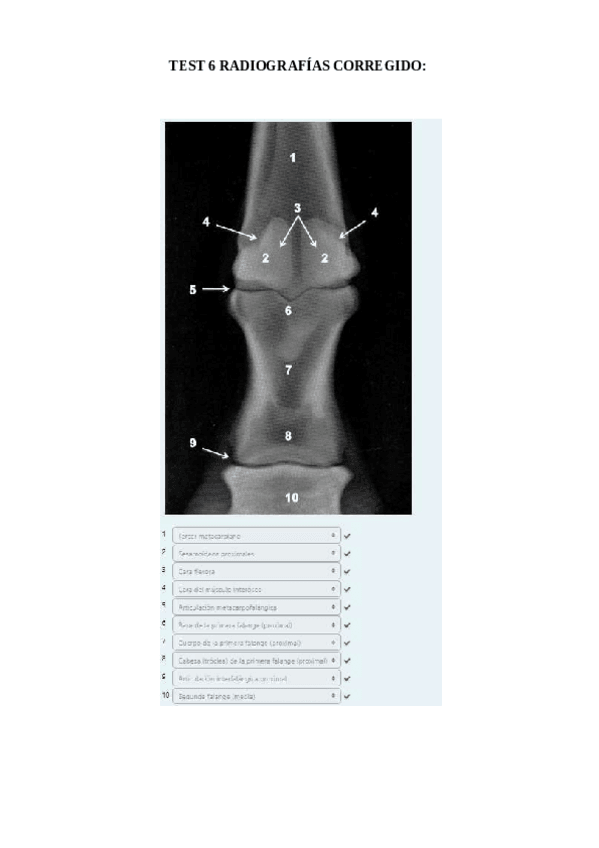

He publicado nuevos apuntes de 1º EMBRIOLOGÍA Y ANATOMÍA I: TEST-6-radiografias-corregido.pdf

9 páginas